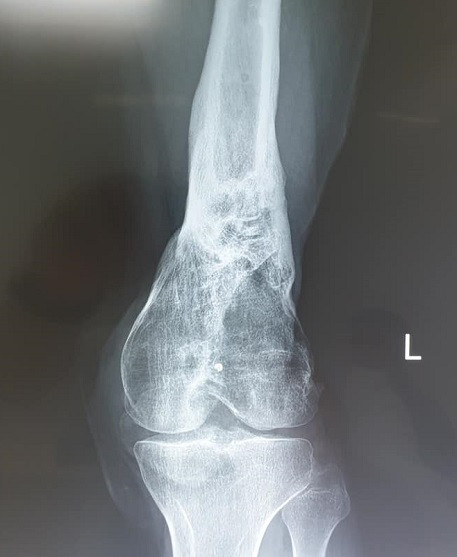

Chia sẻ với phóng viên báo Nhân Dân điện tử, BS Tùng kể, năm năm trước, Đào Quang H (24 tuổi) đang là sinh viên năm thứ nhất vừa nhập học tại một trường Đại học trên địa bàn, được bệnh viện tuyến dưới và gia đình chuyển đến Bệnh viện Hữu nghị Việt Đức sau khi bị tai nạn xe máy với tổn thương gẫy hở chân trái phức tạp, mất xương trên lồi cầu, liên lồi cầu xương đùi và nhiễm trùng.

Tuy nhiên, lúc này, H phải đối mặt với một sự thật, những khuyết xương đùi và cứng khớp gối, mất gân cơ quanh đùi khiến em đi lại vẫn rất khó khăn. BS Tùng kể về hành trình hồi phục đầy phức tạp của bệnh nhân H: "Phẫu thuật gẫy xương vùng khớp gối có hai yêu cầu trái ngược nhau. Mổ xong gối, bệnh nhân phải bất động nằm im duỗi thẳng thì xương mới có cơ hội liền. Nhưng nếu bệnh nhân không tập gấp duỗi gối, khớp gối sẽ cứng. Bệnh nhân H vốn đã bị nhiễm trùng, đồng nghĩa là em sẽ bị dính và cứng khớp khiến cho chân cứng đơ, không co và duỗi được”. Những trường hợp bị chấn thương như H, gối sẽ cứng và phải chấp nhận tình trạng khó vận động cả đời.

Lần phẫu thuật thứ năm đã diễn ra với việc ghép xương. Trong lần phẫu thuật thứ sáu, bệnh nhân đã được ghép gân cơ tứ đầu đùi bằng gân đồng loại từ người cho chết não và gỡ dính khớp gối (gân cơ tứ đầu đùi là một gân to của cơ thể, ngay trên xương bánh chè giúp khớp gối gấp duỗi). Lần đầu tiên triển khai một kỹ thuật mới, một loạt câu hỏi đặt ra thách thức cả ê kíp: Ghép thế nào trên nền một khớp gối vừa dính vừa cứng? Làm thế nào để ghép mà sau mổ khớp gối vừa gấp tốt mà không mất duỗi, vừa duỗi tốt lại không mất gấp? Ghép thế nào để đủ cho nhu cầu bệnh nhân sinh hoạt hàng ngày?